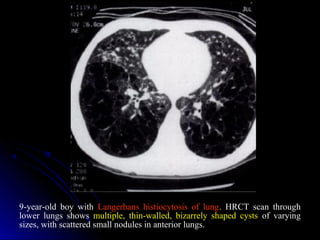

9-year-old boy with Langerhans histiocytosis of lung. HRCT scan through

lower lungs shows multiple, thin-walled, bizarrely shaped cysts of varying

sizes, with scattered small nodules in anterior lungs.